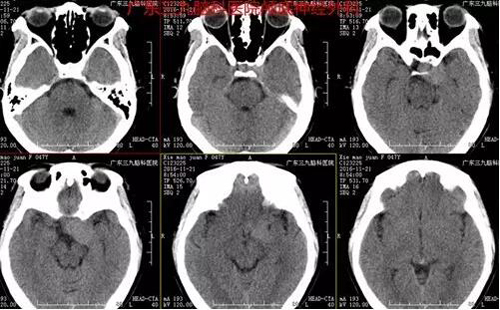

图1:术前CT提示:左侧海绵窦旁稍高均匀密度影

图4:术前术后MR对比提示肿瘤全切除